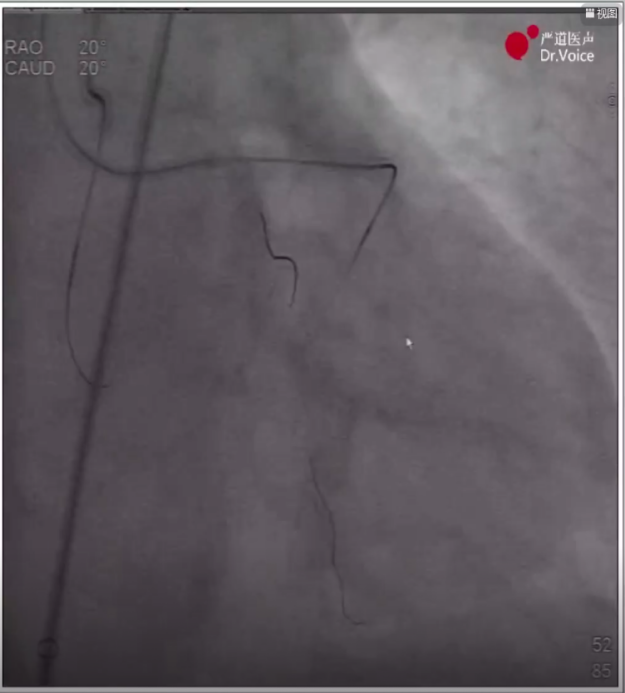

1、术前造影显示LAD近中段弥漫病变,LCX中段完全闭塞,RCA近段完全闭塞、远端形成侧枝循环。

LAD、LCX造影结果

RCA远端侧枝循环

RCA近端完全闭塞